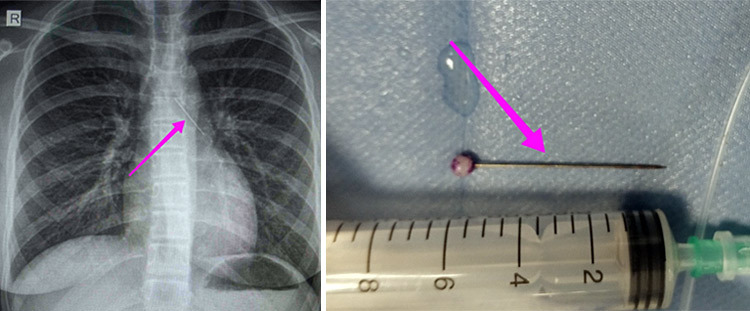

Ανήλικη προσήλθε χθες στο Τ.Ε.Π. του Γ.Ν.Θ. «Ιπποκράτειο», συνοδευόμενη από τους γονείς της, μετά από αναφερόμενη κατάποση ξένου σώματος (καρφίτσα). Από την απεικονιστική διερεύνηση που πραγματοποιήθηκε με ακτινογραφία θώρακος αρχικά και ακολούθως με αξονική τομογραφία θώρακος, διαπιστώθηκε η ύπαρξη αιχμηρού μεταλλικού ξένου σώματος στην αναπνευστική οδό (αριστερός κύριος βρόγχος) και όχι στην πεπτική οδό.

Κατά τη βρογχοσκόπηση διαπιστώθηκε η μετακίνηση και ενσφήνωση του ξένου σώματος στον δεξιό κύριο βρόγχο. Μετά οπό εργώδεις προσπάθειες ολοκληρώθηκε με επιτυχία η αφαίρεση αυτού. Η ασθενής ανένηψε πλήρως εντός της χειρουργικής αίθουσας. Μεταφέρθηκε για παρακολούθηση και νοσηλεία στη Γ’ Παιδιατρική Κλινική.